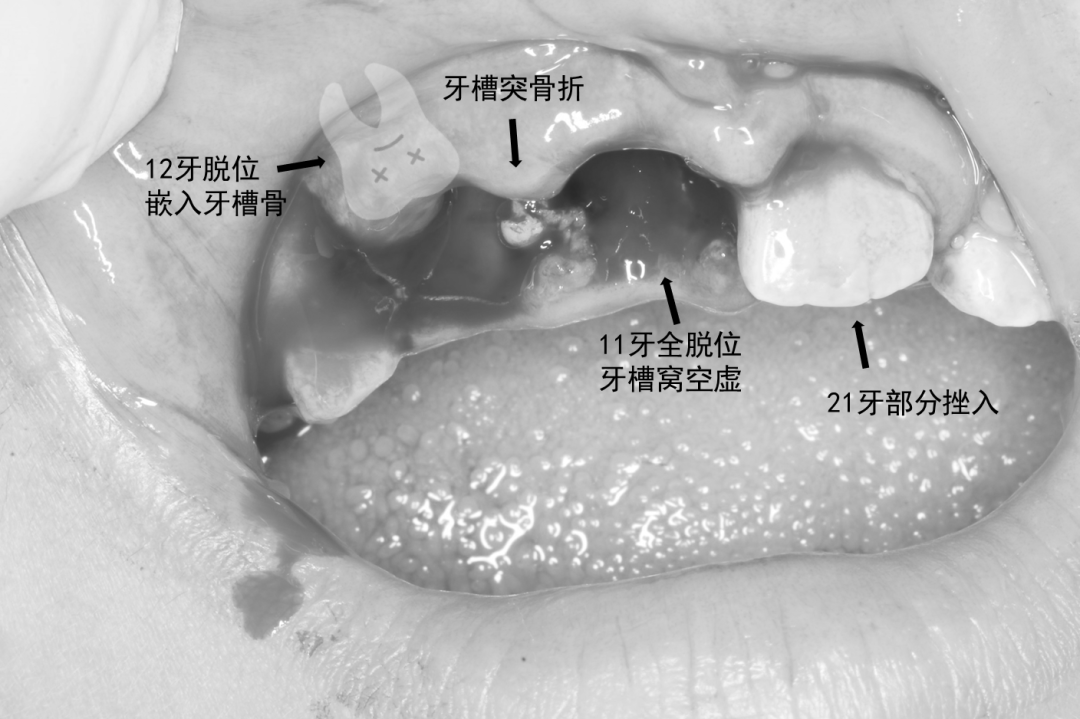

经过口内检查和影像学检查,豆豆掉了一颗门牙,旁边的一颗侧切牙原来没有“失踪”,而是受到大力撞击,牙槽突骨折,那颗侧切牙已经深入牙龈,嵌入到牙槽骨中。

另外一颗门牙也有部分挫入,还伴有牙龈撕裂、嘴唇挫裂伤。

经过急诊医生处理,对脱出的门牙进行再植,对嵌入的侧切牙和上前牙牙槽突骨折进行复位,用纤维带为受伤牙齿做好固定,对牙龈挫裂伤进行清创缝合。